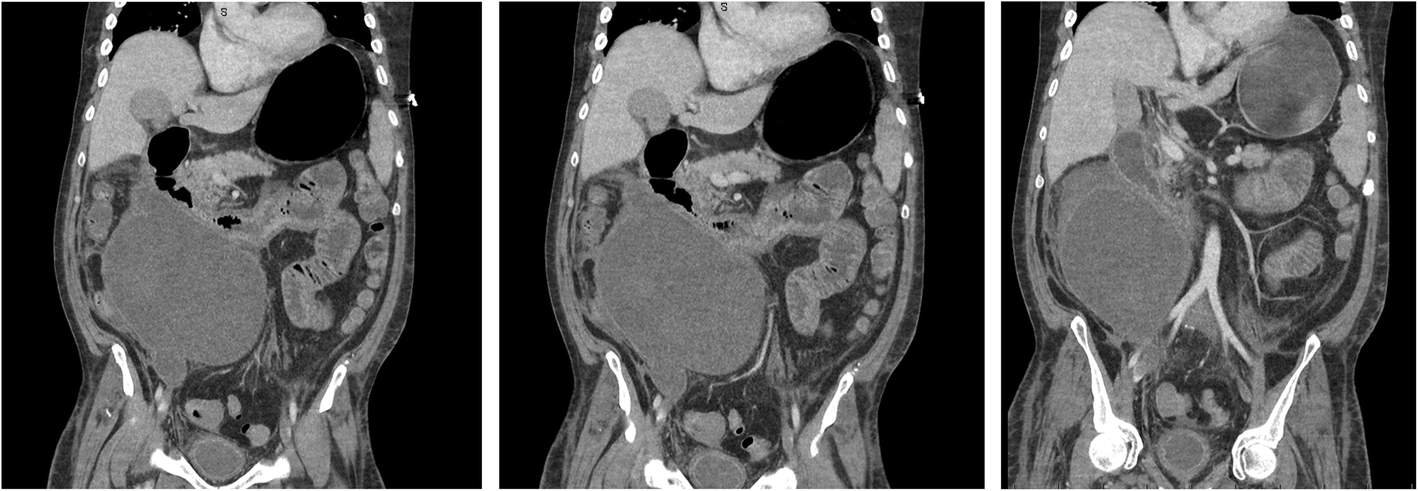

Contrast CT revealed interval increase in the size of the haematoma, compression of D3 (distal duodenum) and resultant gastric distension causing left ventricular distortion (Fig. 5).

Fig. 5

Coronal CT sections showing a large retroperitoneal haematoma, duodenal compression and gastric distension and a distorted left ventricle

Bild vergrößern